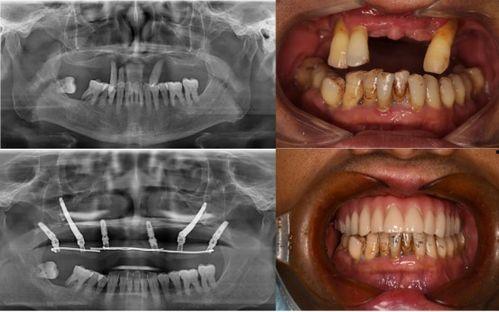

据患者们反映,他们在种植牙的过程中,遇到了种种问题。有的患者表示,医生在手术过程中操作不规范,导致种植牙失败;有的患者则抱怨,术后恢复期过长,而且效果并不理想。更有甚者,竟然出现了种植牙植入后,牙槽骨吸收的情况。

这起事件也引起了相关部门的关注。据知情人士透露,当地卫生部门已经介入调查,对这家口腔医院进行了全面检查。检查结果显示,这家医院在种植牙过程中确实存在一些不规范的操作。目前,相关部门已经对该医院进行了处罚,并要求其立即整改。

对于这起事件,口腔医学专家也给出了自己的看法。他们认为,种植牙是一项高风险的手术,需要医生具备丰富的经验和专业的技术。而这家口腔医院在种植牙过程中出现的问题,反映出我国口腔医疗行业在规范化、专业化方面还存在不少问题。